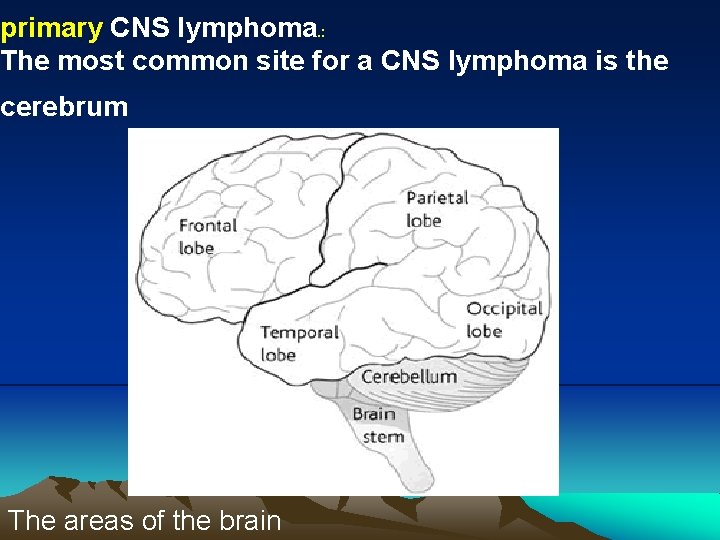

primary CNS lymphoma. : The most common site for a CNS lymphoma is the cerebrum The areas of the brain